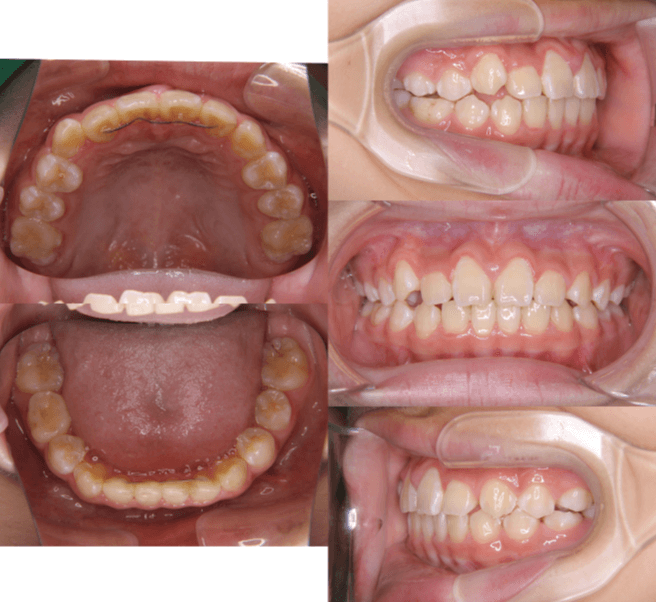

| 年齢・性別 | 8歳9ヶ月の女児 |

|---|---|

| 主訴 | 歯並びの乱れを気にされて来院された患者様です。将来的なスペース不足と歯のねじれ(翼状捻転)が懸念されました。 |

| 治療期間・回数 | 2年10ヶ月・19回 |

| 費用 | 430,000円(税別) |